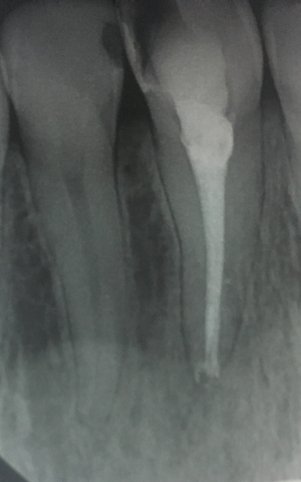

Когда снова пришла, он запломбировал каналы и поставил пломбу. И уже третий день подряд болит зуб. То сильная боль, то терпимая. Перепадами. Когда уже не могу терпеть, пью обезболивающие. Еще принимаю противовоспалительные.

Скажите, должны быть такие боли и пройдут ли они, или это признак воспаления и нужно перепломбировать все?

Конечно, при постоянной пломбировке зуб беспокоить уже не должен. Судя по методам лечения, у вас обострение хронического периодонтита, но оставлять открытым канал на полоскание нельзя, это неграмотное лечение. А также беспокойство зуба, возможно, связано с недолеченным процессом хронического воспаления, обратитесь к другому стоматологу на лечение данного зуба.